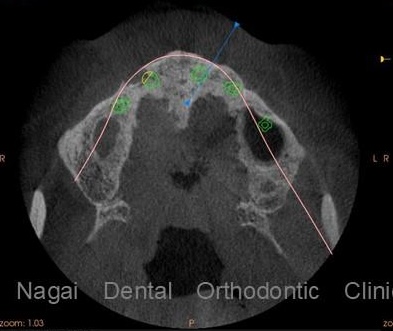

1. 精密なCT診断と3Dシミュレーション

全症例で歯科用CTを使用。

骨の厚み・神経・血管の位置を立体的に把握し、最適な埋入位置を事前にシミュレーションします。

「見えない部分まで可視化して計画する」ことで、より安全で確実な手術を可能にしています。